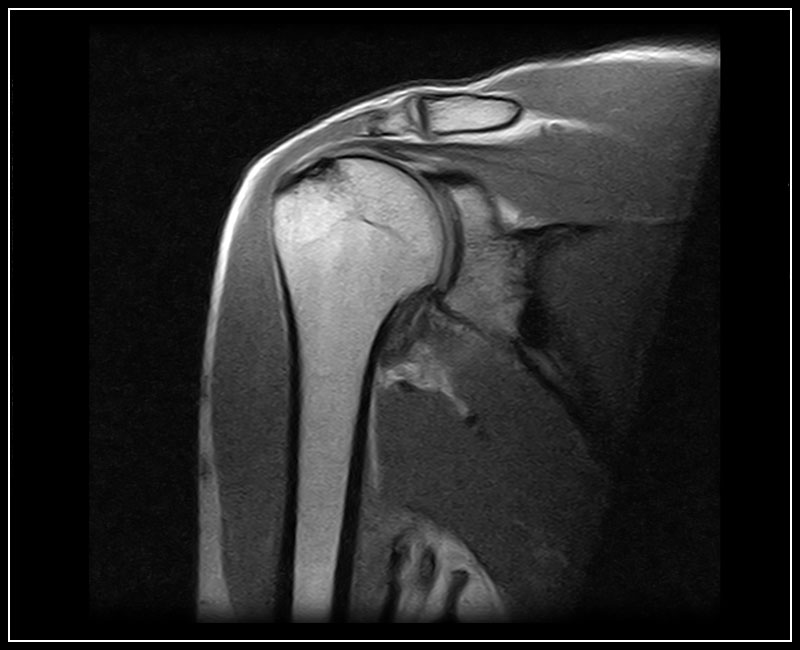

Klinické snímky